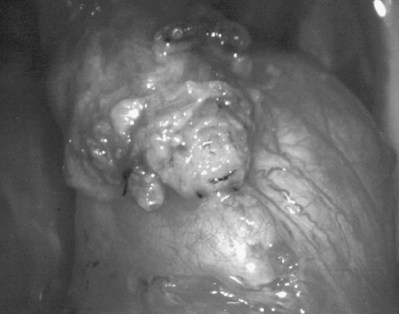

After opening the tunica vaginalis, the epididymis is inspected under the operating microscope. An anastomotic site is selected above the area of suspected obstruction, proximal to any visible sperm granulomas, where dilated epididymal tubules are clearly seen beneath the epididymal tunica (Fig. 22–29). A relatively avascular area is grasped with sharp jeweler’s forceps and the epididymal tunica tented upward. A 3- to 4-mm buttonhole is made in the tunica with microscissors to create a round opening that matches the outer diameter of the previously prepared vas deferens. The epididymal tubules are then gently dissected with a combination of sharp and blunt dissection until dilated loops of tubule are clearly exposed (Fig. 22–30). If the level of obstruction is not clearly delineated after the buttonhole opening is made in the tunic, a 70-µm diameter tapered needle from the 10-0 nylon microsuture is used to puncture the epididymal tubule beginning as distal as possible and fluid is sampled from the puncture site. When sperm are found, the puncture sites are sealed with microbipolar forceps, a new buttonhole is made in the epididymal tunic just proximally, and the tubule is prepared as described previously.

Figure 22–29 An anastomotic site is selected above the area of suspected obstruction, proximal to any visible sperm granulomas, where dilated epididymal tubules are clearly seen beneath the epididymal tunica, as marked by an arrow.